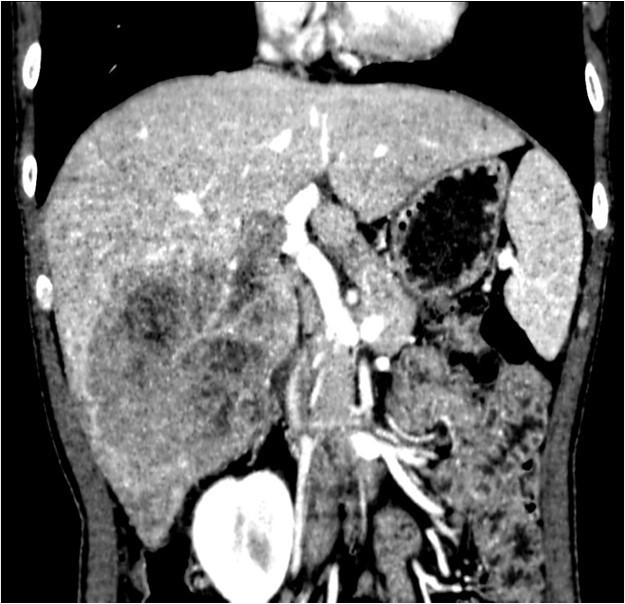

体查:未见阳性体征 实验室检查: WBC 7.24× 109/L, N 48.1%, Hb 159g/L, PLT 117× 109 /L ,PT 12.5s ; HBsAg+, HBcAb+,HBeAg+;HBV-DNA5.33× 106 IU/mL ALT 240 U/L, AST 154 U/L, ALB 36.9g/L, TBIL 13.1umol/L AFP 6270 ug/L ICG 15分钟滞留率 4.5%;Child-Pugh A级 CT提示肝S5、S6肝细胞癌并门静脉右支癌栓形成

诊断: • 肝细胞癌 • 门静脉右支癌栓 治疗:右半肝切除、门静脉取癌栓、胆囊切除术 术后病理: • 肝细胞癌,梁索型,II级,癌旁组织呈门脉性肝硬化改变 • 门静脉内组织呈现肝细胞癌改变伴坏死,符合癌栓改变